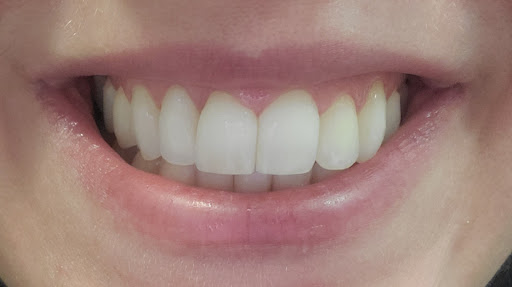

Photos